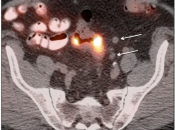

Metastases:

The most common sites of metastatic disease include the lymph nodes (regional & distant), liver, lung, peritoneal cavity, bones, brain and adrenal glands.

False Negatives:

- If there are multiple areas of intense bowel uptake (a common finding), the primary tumor can be difficult to locate — especially if the associated soft tissue lesion is small, which can be undetectable with CT imaging.

- Nodes under 8.0 mm may be non-avid only because they are beneath the resolution of PET (metastatic nodal assessment is discussed in detail, here).

- If < 8.0 mm, even mild uptake in a regional node is “highly suspicious”.

- If < 8.0 mm, even non-avid regional nodes are worrisome, and are considered “indeterminate”.

- Mucinous adenocarcinomas and necrotic tumors can have low avidity for FDG.